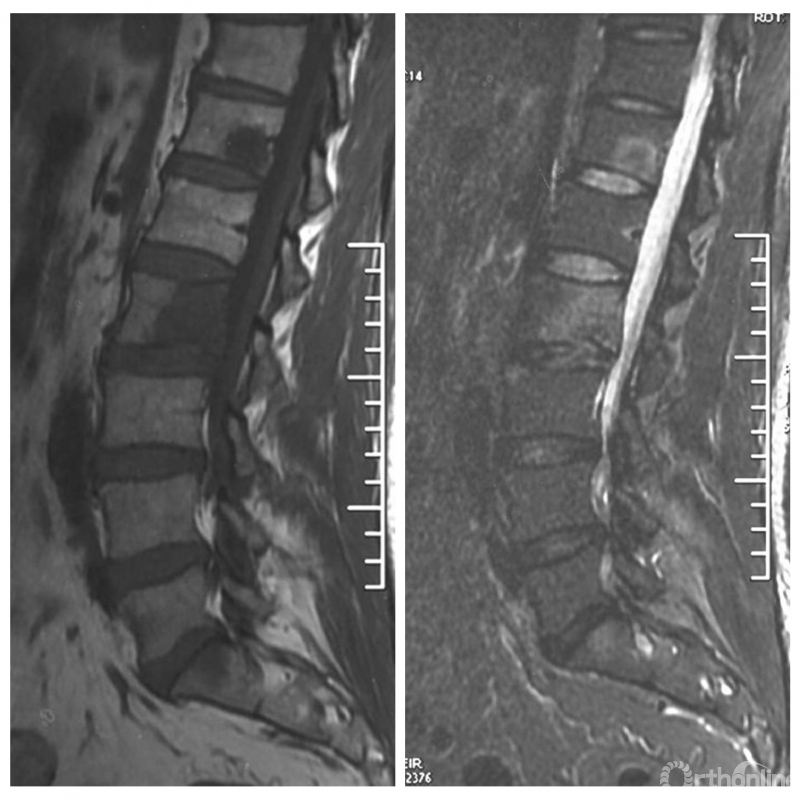

患者腰椎转移瘤术后9个月,因“腰痛伴右下肢疼痛麻木2个月”再次入院。既往在PVP术后曾行化疗及服用埃克替尼靶向药物维持治疗,查体一般状况良好,自主行走,右大腿前外侧麻木。

入院影像学资料

经脊柱转移瘤专业评估,ESCC分级为Grade2,对放疗不敏感;SINS评分8分,中度不稳。Karnofsky功能状态评分90%,预计生存时间6个月。NOMS流程建议分离手术和SRS。

常规分离手术可进行360°脊髓减压,充分固定恢复脊柱稳定;但由于其暴露范围广泛,创伤较大,并不适宜患者当前治疗。

为进一步减少创伤,获得更好的综合疗效。骨采用经皮内固定的微创杂交技术,暨经皮内固定结合小切口分离手术,手术失血900ml,术后7天出院。